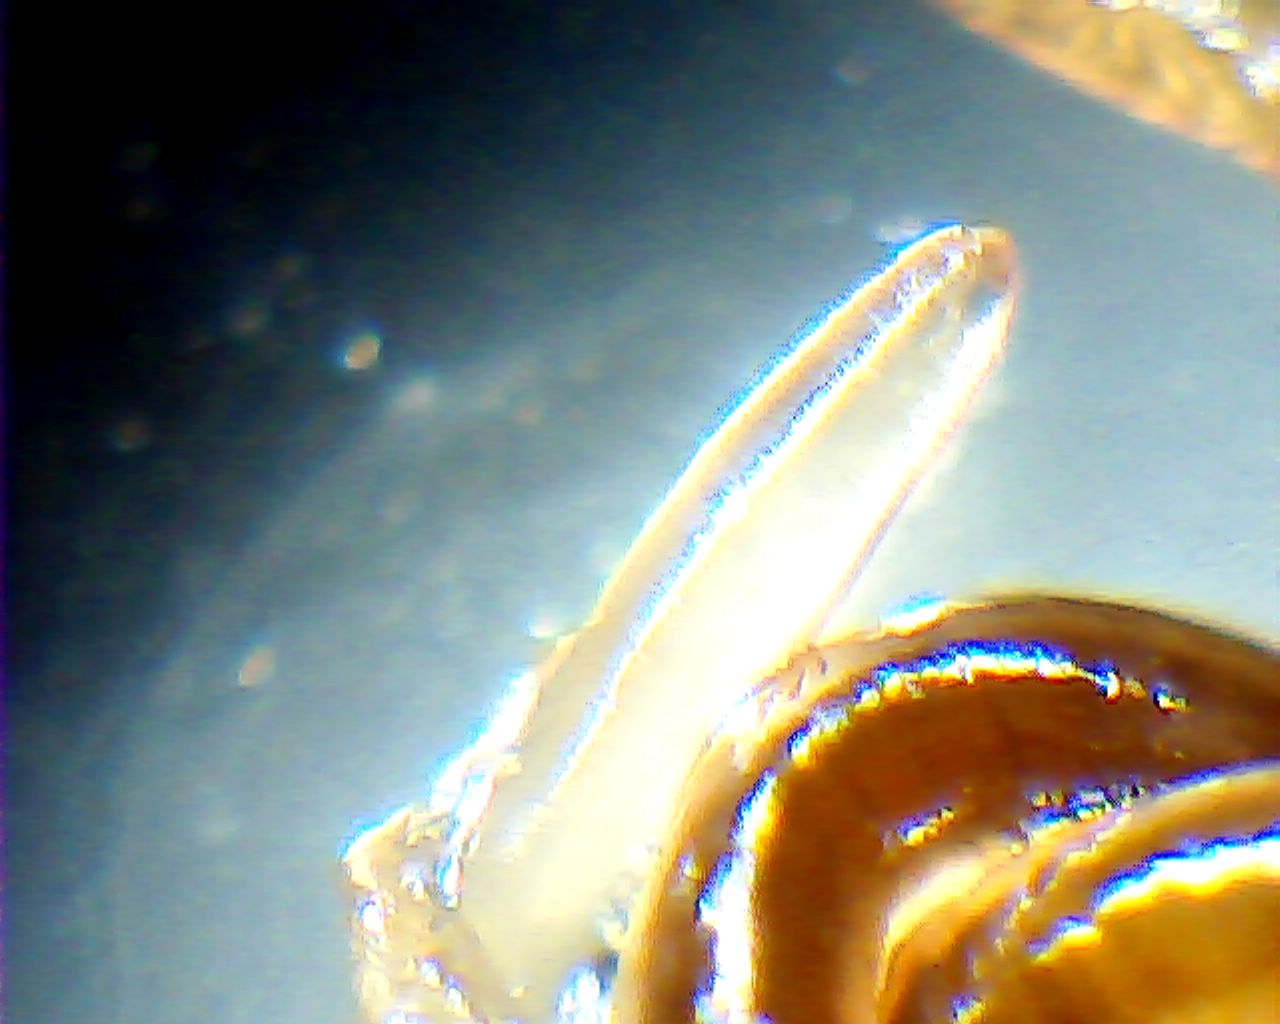

Червяк-паразит Eustrongylides excisus под микроскопом.

– Ещё осенью 2012 года я услышал, что в мясе хищной рыбы, которую выловили в плавнях, появились новые паразиты, – рассказал Владимир Никифоров, – я попросил всех коллег, если они поймают рыбу – дать на исследование. В марте мне принесли десяток окуней. В каждой рыбине было от 5 до 35 слизистых капсул – личиночная стадия червя. Они распологались по всей длине окуней.

По словам Владимира Никифорова, он проконсультировался со многими учёными из Украины и России и сделал вывод, что обнаруженный червь-паразит является Eustrongylides excisus. Его уже обнаружили в Волге и, скорее всего, он был принесён оттуда цаплями.

– Среди местных рыбаков существует мнение, что зараженную этим паразитом рыбу можно есть, – говорит учёный, – но их российские коллеги утверждают, что личинки нематод из семейства Dioctophymidae (в том числе паразит, обнаруженный в кременчугской рыбе – ред.) опасны для здоровья человека и животных. При попадании в организм у человека наблюдается картина, похожая на пиелонефрит, цистит или уретрит.

– Чтобы безопасно есть днепровскую рыбу, её нужно поддать термической обработке в течение не менее 20 минут, – говорит доктор наук, – но после этого не многие захотят эту рыбу есть. К тому же, вы получите мало удовольствия, когда почувствуете на зубах слизистую капсулу, раскусив которую у вас во рту окажется несколько червячков.

Высохшая капсула от яйца паразита и высохшие «молодые» червяки.